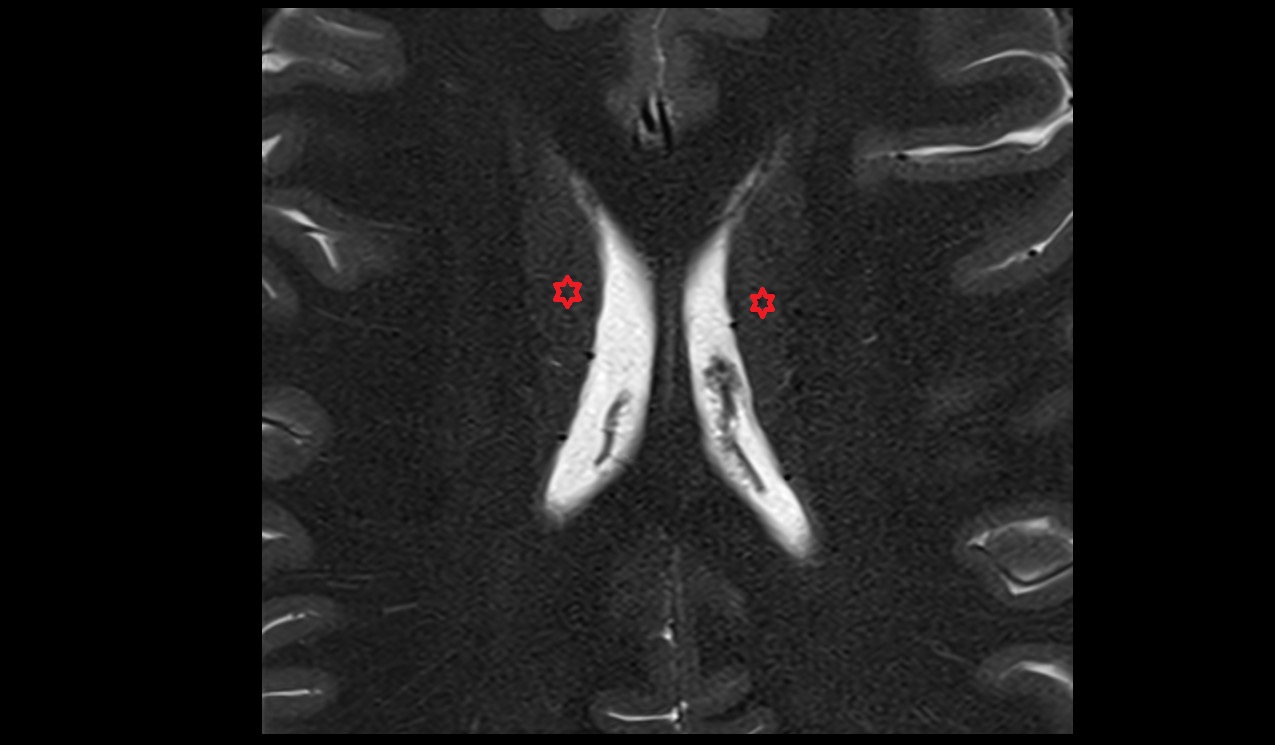

- Body of hippocampus

- Head of hippocampus

- Tail of hippocampus

- Hippocampus